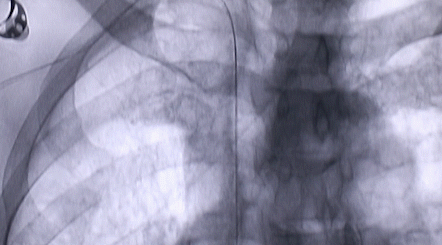

按照術(shù)前制定的方案,郭穎強(qiáng)主任和楊金保博士首先嘗試開(kāi)通閉塞的右腎動(dòng)脈,但由于血栓機(jī)化、鈣化嚴(yán)重,右腎動(dòng)脈難以開(kāi)通。遂謹(jǐn)慎擴(kuò)張狹窄的左腎動(dòng)脈,并成功植入一枚支架。之后經(jīng)過(guò)反復(fù)旋磨、抽吸,順利開(kāi)通髂動(dòng)脈,但腹主動(dòng)脈閉塞段仍難以擴(kuò)通。此時(shí),患者居高不下的血壓很快恢復(fù)到正常水平。